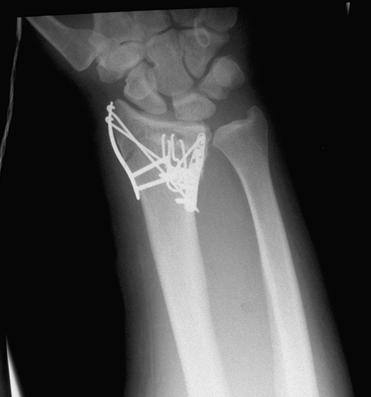

Case 1 Postop